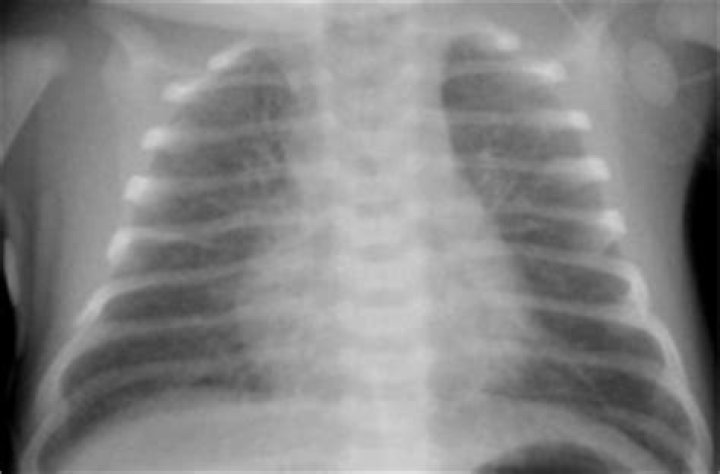

What are the stages of bronchopulmonary dysplasia?

Four stages of radiographic changes of BPD have been described: stage I, which is RDS seen in the first week; stage II, which includes generalized haziness and plethora in the second week; stage III, which involves cystic changes and stranding in the third week; and stage IV, which is characterized by hyperinflation, ...